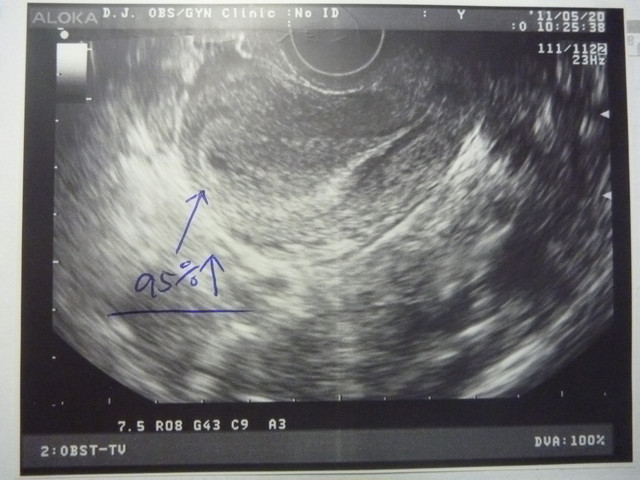

5/20(約2週多)

去找我之前常去的"大佳婦產科"的林醫師報到!!

掃完超音波之後~林醫師照慣例給了我一張照片好幫bb寫日記~

今天的bb還很小~目前初估2週左右~

95%應該就是一個小小懷孕囊的小寶貝!!

那5%是啥?!林醫師說可能是子宮外孕~但他有連卵巢輸卵管都一起照~

看起來是沒問題的~

所以基本上外孕的機率不高!!

那麼....就再等5/30門診吧!!到時就可以確定囉!!